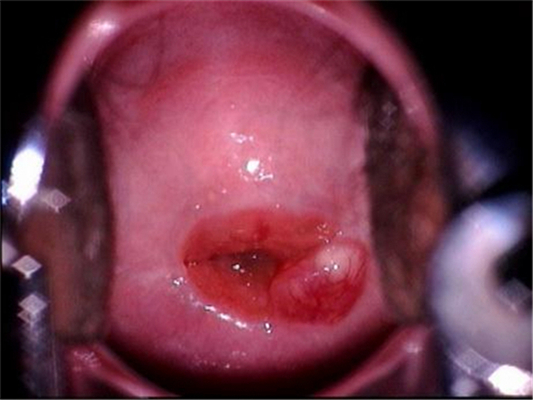

子宮頸炎圖片

宮頸炎